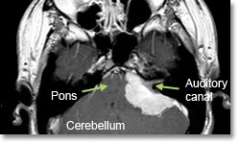

Meningioma Cerebellopontine Angle

Location - Cerebellopontine angle (on the side of the brainstem)

Common Symptoms

- Loss of hearing. Facial muscle weakness. Dizziness. Unsteadiness and incoordination, hydrocephalus (increased pressure inside the brain), voice and swallowing difficulties.